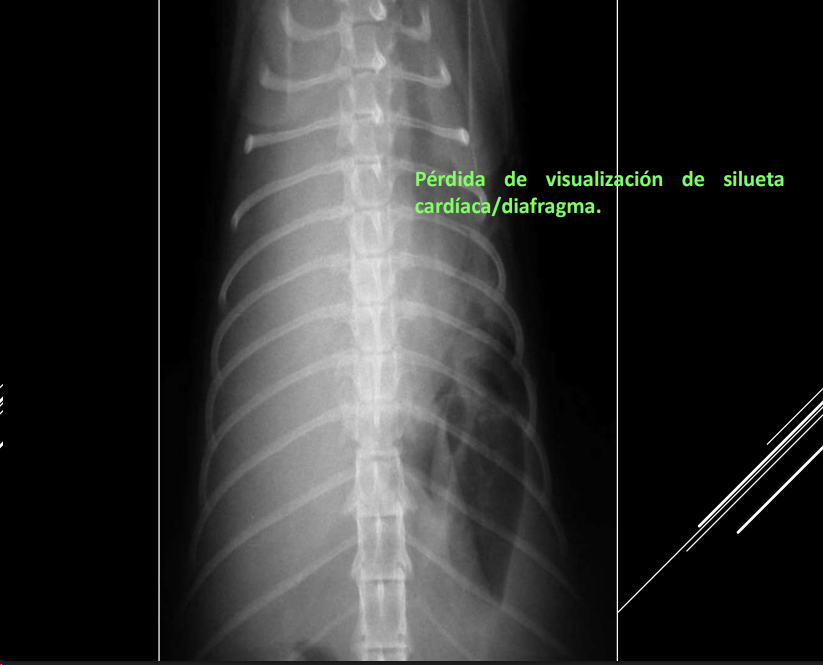

Derrame pleural

- Líquido en espacio pleural (uni/bilateral).

- RX: